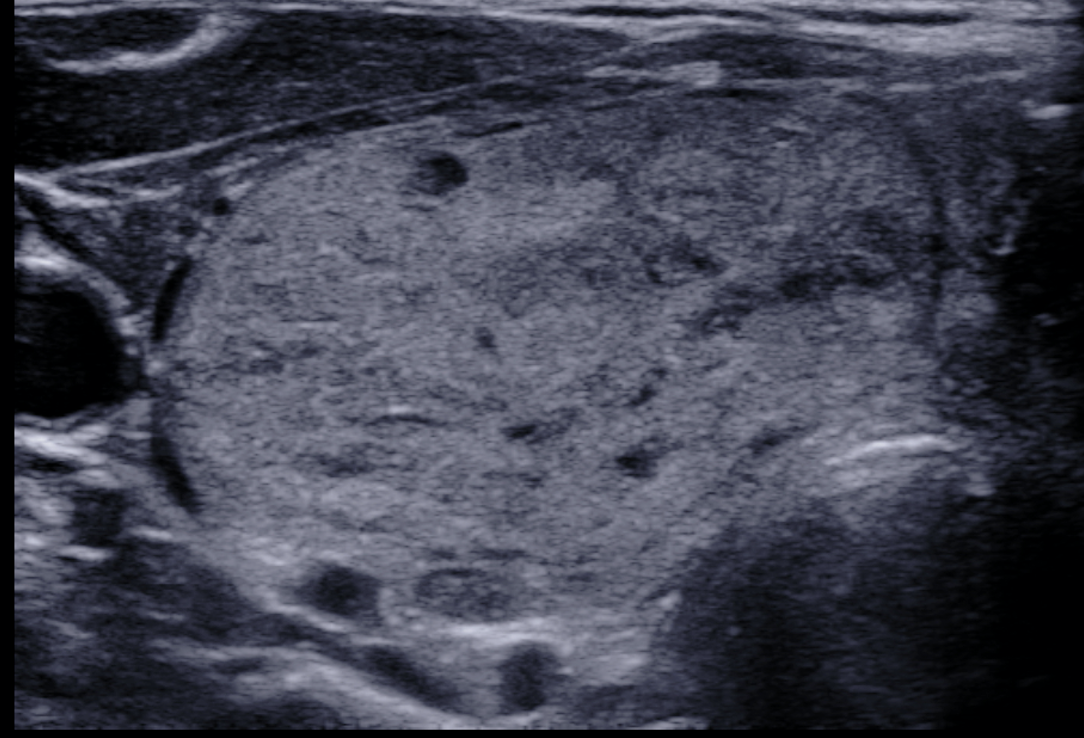

TI-RADS 3. Очаговые структуры, требующие динамического наблюдения без выполнения биопсии (гипер- или изоэхогенные образования с ровными контурами, в том числе на фоне аутоиммунного тиреоидита; кальцинированные узлы по типу “яичной скорлупы”) (рис. 2).

Рис. 2. Категория TI-RADS 3: а – изоэхогенный очаг (стрелки), окруженный тонким хало (узловой зоб); б – гиперэхогенный очаг округлой формы, с четкими контурами, тонким гипоэхогенным ободком на фоне аутоиммунного тиреоидита; в – кальцинированный узел по типу “яичной скорлупы”.